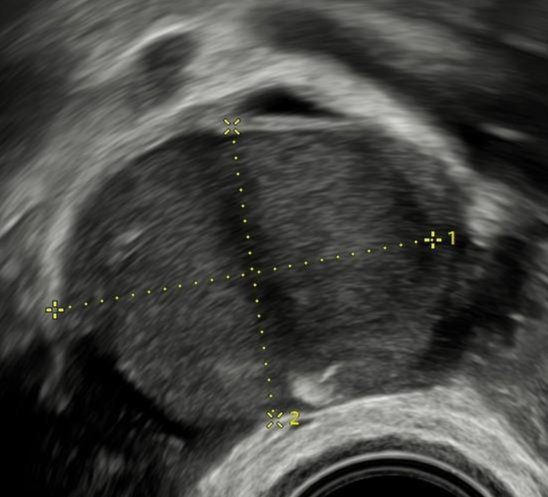

Ultrazvuk: dvoukomorová endometriózní cysta vaječníku.V praxi jsem se velmi často setkával s klientkami, které za sebou měly několik operací pro bolesti v podbřišku nebo neplodnost a jejich obtíže přetrvávaly po operaci dále. Ložiska endometriózy, zvláště ta hluboká, byly často přehlédnuta, nebo je operační tým neuměl vyřešit a žena tak zbytečně podstoupila další operační zákrok. Našim cílem bylo (a je) klientku správně vyšetřit a pokud si řešení vyžádá operační intervenci, tak odstranit všechna ložiska, která způsobují problém.

Endometriózní cysta vaječníku.